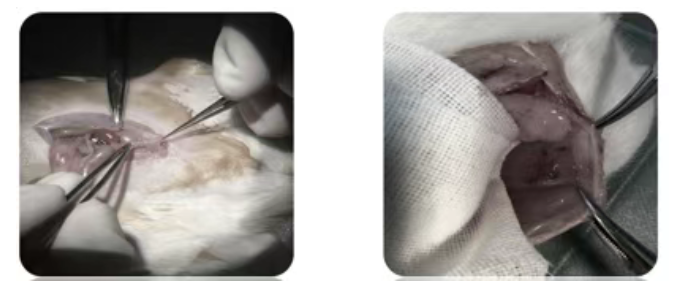

供体与受体小鼠均需皮下注射苯甲酸雌二醇(100μg/kg),1 次 / 天陆续在 5 天,模拟生理激素环境; 供体小鼠麻醉后沿腹中线切开取子宫,将子宫立即置于 4℃冷生理盐水中(冰上保存),确保组织活性; 图1 供体小鼠子宫 受体小鼠麻醉后,在腹壁做 1cm 切口,将子宫组织松散缝合于腹壁内表(避免过紧影响血供),且确保子宫内膜面朝腹壁,每侧缝合 1 块组织; 图2 受体小鼠子宫移植过程 术后每隔 1 天注射苯甲酸雌二醇,持续 2 周,为异位灶生长给予适宜条件。 1)大体观察:术后2周开腹查看病灶是否形成。通常表现为充满液体的囊泡状结构,并有明显血管分布。 图3 小鼠子宫异位灶大体情况 异位灶为囊性不规则形态,呈半透明色,囊内含淡黄色或半透明液体,囊壁表面有细小血管形成。 2)组织学检测:HE染色&免疫组化。HE染色结果在显微镜下观察到典型的子宫内膜样结构,即子宫内膜腺体和间质细胞,是模型成功的最关键证据。免疫组化检测子宫内膜中增殖细胞核抗原(PCNA)、血管内皮生长因子(VEGF)、E-钙粘蛋白等增殖和血管生成相关基因的表达。 图4 小鼠子宫异位灶病理学检测(H.E. 染色,40X) 纤维结缔组织及横纹肌组织内查见子宫内膜样腺体及间质,部分腺体扩张明显,病变符合子宫内膜异位。 图5 小鼠子宫异位灶PCNA、VEGF和E-钙粘蛋白免疫组化结果[2] 注:EM为未经治疗的EMs小鼠,N10和N20分别是EM加川陈皮素组小鼠(10kg/kg,20kg/kg) 3)行为学评估(疼痛表型):顺利获得测量小鼠对机械刺激(如von Frey纤毛刺激腹部)或热刺激的敏感性阈值,来评估其是否出现类似人类的痛觉超敏(Allodynia) 和痛觉过敏(Hyperalgesia)。 4)生育力评估:模型小鼠与雄鼠合笼,记录受孕率与窝产仔数等指标。 [1]Bashir ST, Redden CR, Raj K, Arcanjo RB, Stasiak S, Li Q, Steelman AJ, Nowak RA. Endometriosis leads to central nervous system-wide glial activation in a mouse model of endometriosis. J Neuroinflammation. 2023 Mar 6;20(1):59. [2]Wei X, Shao X. Nobiletin alleviates endometriosis via down-regulating NF-κB activity in endometrio 技术沉淀:深耕动物模型领域多年,熟悉EMs模型的关键节点(如激素注射剂量、移植位置精度、评估指标选择),能避免 “术后异位灶不存活”“模型重复性差” 等常见问题; 严格质控:从SPF级动物的饲养管理,到手术操作的标准化流程,再到多维度的模型评估,每一步都有专人把控,确保交付的模型 “即拿即用”; 定制化服务:可根据客户研究需求,调整模型类型(如异种移植模型、特定基因型同种异体模型)、移植位置、评估指标,为不同研究方向(如发病机制、药物筛选)给予适配方案。